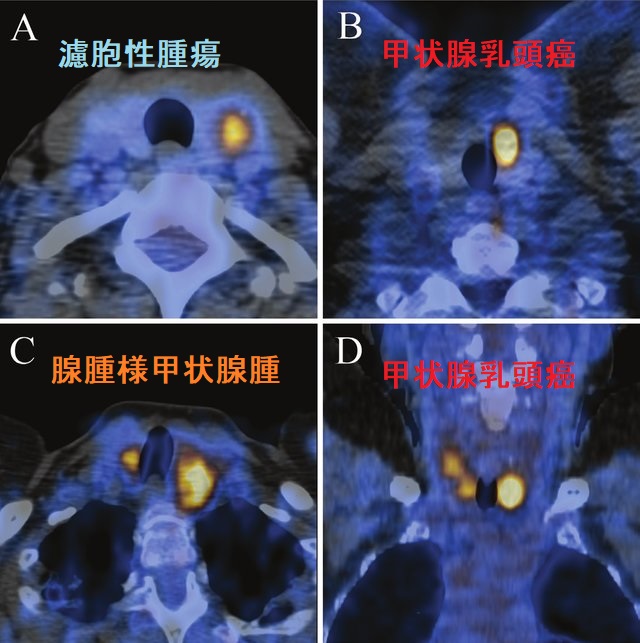

下の写真を見れば一目瞭然。甲状腺内の結節性病変は、良悪性に関係なく同じに見えます。SUVmax(放射線の最大集積値)だけでは判定できません。

- A;濾胞性腫瘍 SUVmax4.4

- B;甲状腺乳頭癌 SUVmax11.8

- C;腺腫様結節(腺腫様甲状腺腫) SUVmax6.4-7.8

- D;多発性甲状腺乳頭癌 SUVmax4.5-8.1

(Mol Imaging Radionucl Ther. 2017 Oct 3;26(3):93-100.)